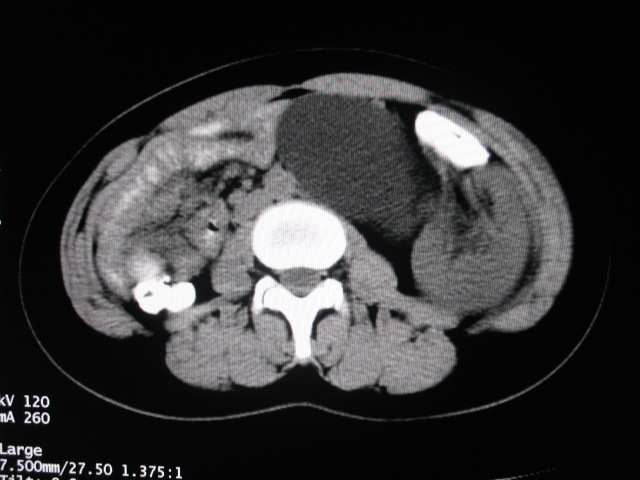

女,28岁,自觉腹部包块一年余

左侧为扩张的输尿管,一直延续到膀胱,那么它的上端应该是扩张的肾盂,但是在他的下方我们看到一个比较正常的肾,所以考虑左侧重复肾盂输尿管畸形。

考虑左侧双肾盂双输尿管畸形,其中一输尿管末端梗阻(不排除异位开口可能)并相应之肾盂及输尿管明显扩张积水。

左侧重复肾、双输尿管畸形。重复肾一般上位肾发育不良,易合并积水。

术后证实是左侧双肾盂双输尿管畸形,巨输尿管巨肾盂症